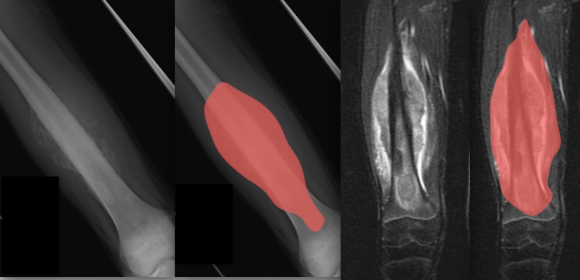

手術前的 X-ray 顯示腫瘤侵犯骨骼的位置離關節面較遠,可以保留病患的骨骺與關節。MRI 亦相當清楚的顯示腫瘤的範圍。